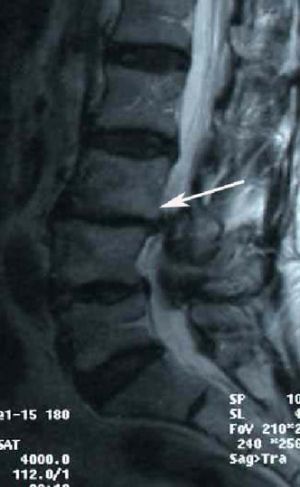

Рис.4. МРТ поясничного отдела позвоночника. Ретролистез L3  позвонка. Стрелкой указано  смещение L3 позвонка кзади.

По старой классификации этот вид листеза назывался псевдоспондилолистезом, т.к. при этой форме не выявлялось ни слабости дужки позвонка, ни недоразвития фасеточных суставов. Позднее, эта форма спондилолистеза названа дегенеративной, т.к. ее причиной были изменения позвоночника по типу остеоартрита («старение позвоночника»).  Дегенеративный листез в подавляющем большинстве случае встречается у людей после 40 лет. Женщины страдают данной формой листеза в 4 раза  чаще мужчин. Наиболее часто дегенеративный листез встречается на уровне L4-L5, однако может встречаться на уровне L3-L4 и L5-S1. Дефекты дужки при этой форме встречаются редко, в результате листеза развивается стеноз (сужение) позвоночного канала с различной степенью выраженности болей в пояснице.